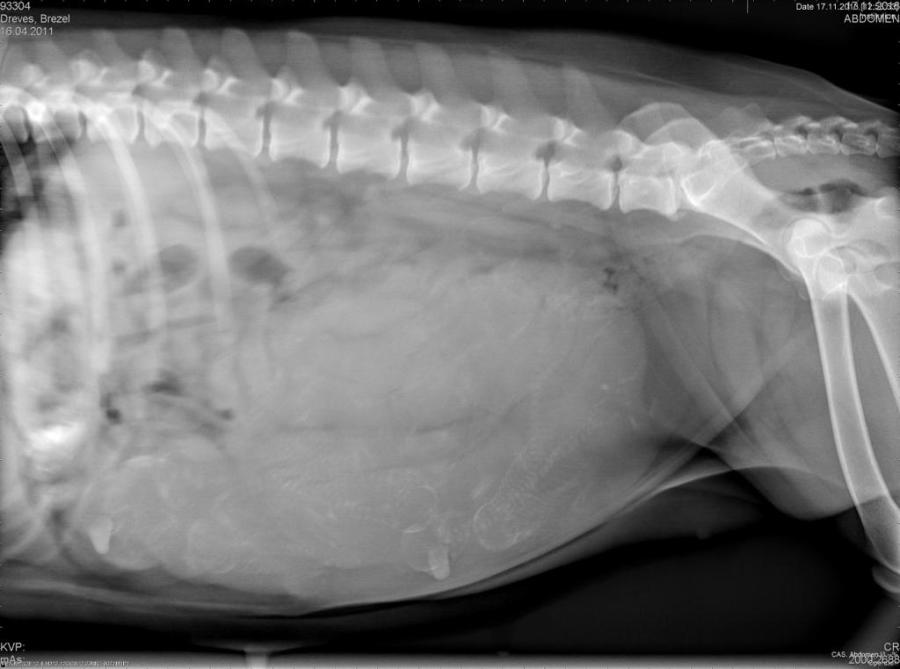

17.11.2018

Gestern hat mein Sohn unsere restlichen Apfel gepflückt  und Brezel war mit im Garten. Unbemerkt hat sie leider sehr sehr viele Äpfel gefressen. Heute hatte sie dann schlimme Bauchweh, so dass wir vorsichtshalber in die Tierklinik gefahren sind. Zur Abklärung wurde ein Röntgenbild angefertigt, aber es war zum Glück alles ok, bis auf die Bauchweh. Dagegen gab es ein Medikament. Jetzt wissen wir aber auch, dass wir einen eher großen Wurf erwarten!